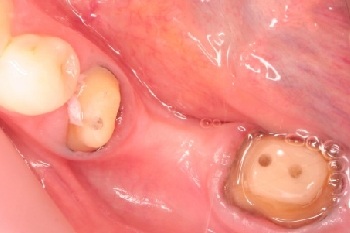

千葉市緑区 T.I様 左下567番 メタルボンドブリッジ修復

担当歯科医師:川津良介理事長